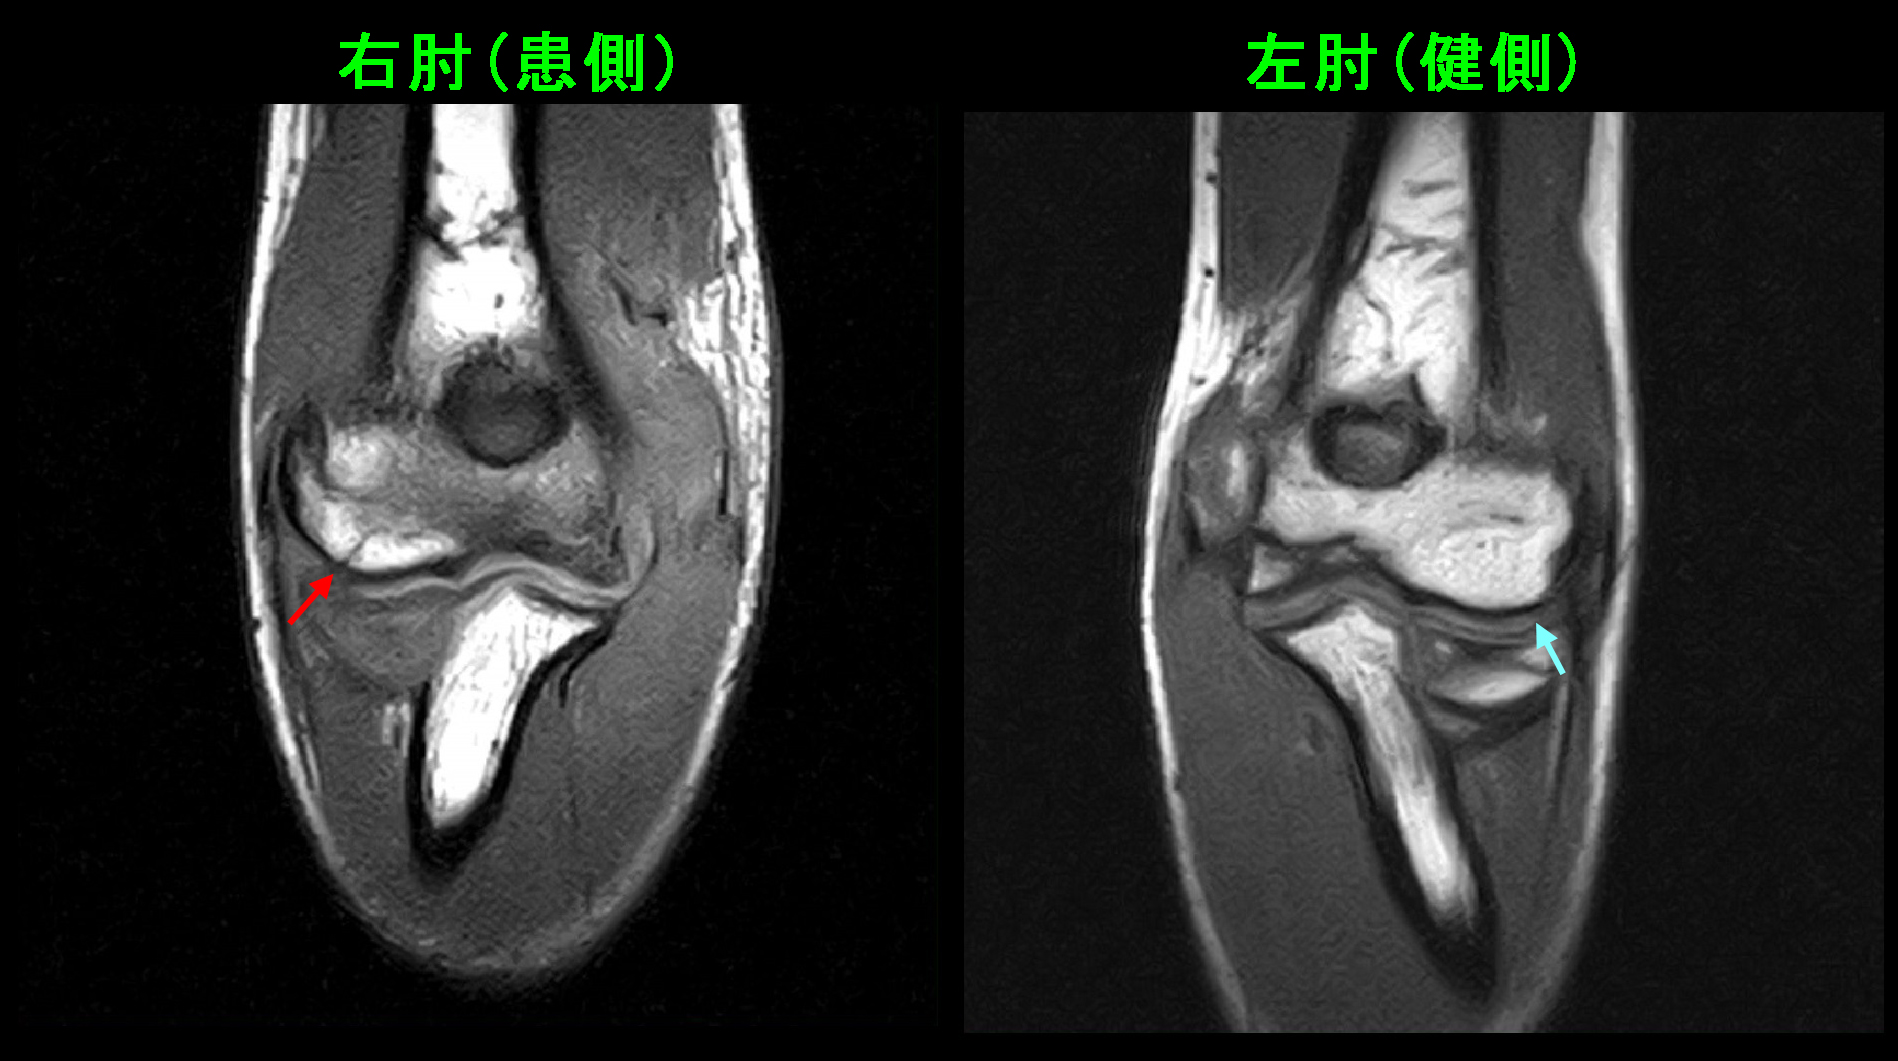

13才男 MR2.jpg

T1という条件の冠状断(前後像)で右肘上腕骨の外側関節部分の赤矢印が骨折線と判断されます。

13才男 MR3.jpg

違うT1の冠状断では上腕骨の内側部分(赤丸の領域)で骨が黒っぽく(低輝度と)なっていて、これも骨の損傷を示しています。初診時のSTIRの冠状断で上腕骨の内側部分(黄色丸領域)が白っぽかった(高輝度を呈していた)のはこの骨損傷に起因していたのです。

13才男 MR4.jpg

T1の水平断(横断面)では上腕骨の関節部分の大半が低輝度となっており、骨損傷が広範囲に起きていることが把握できます。また、患側の右肘は左肘に比較して重度に腫脹しています。